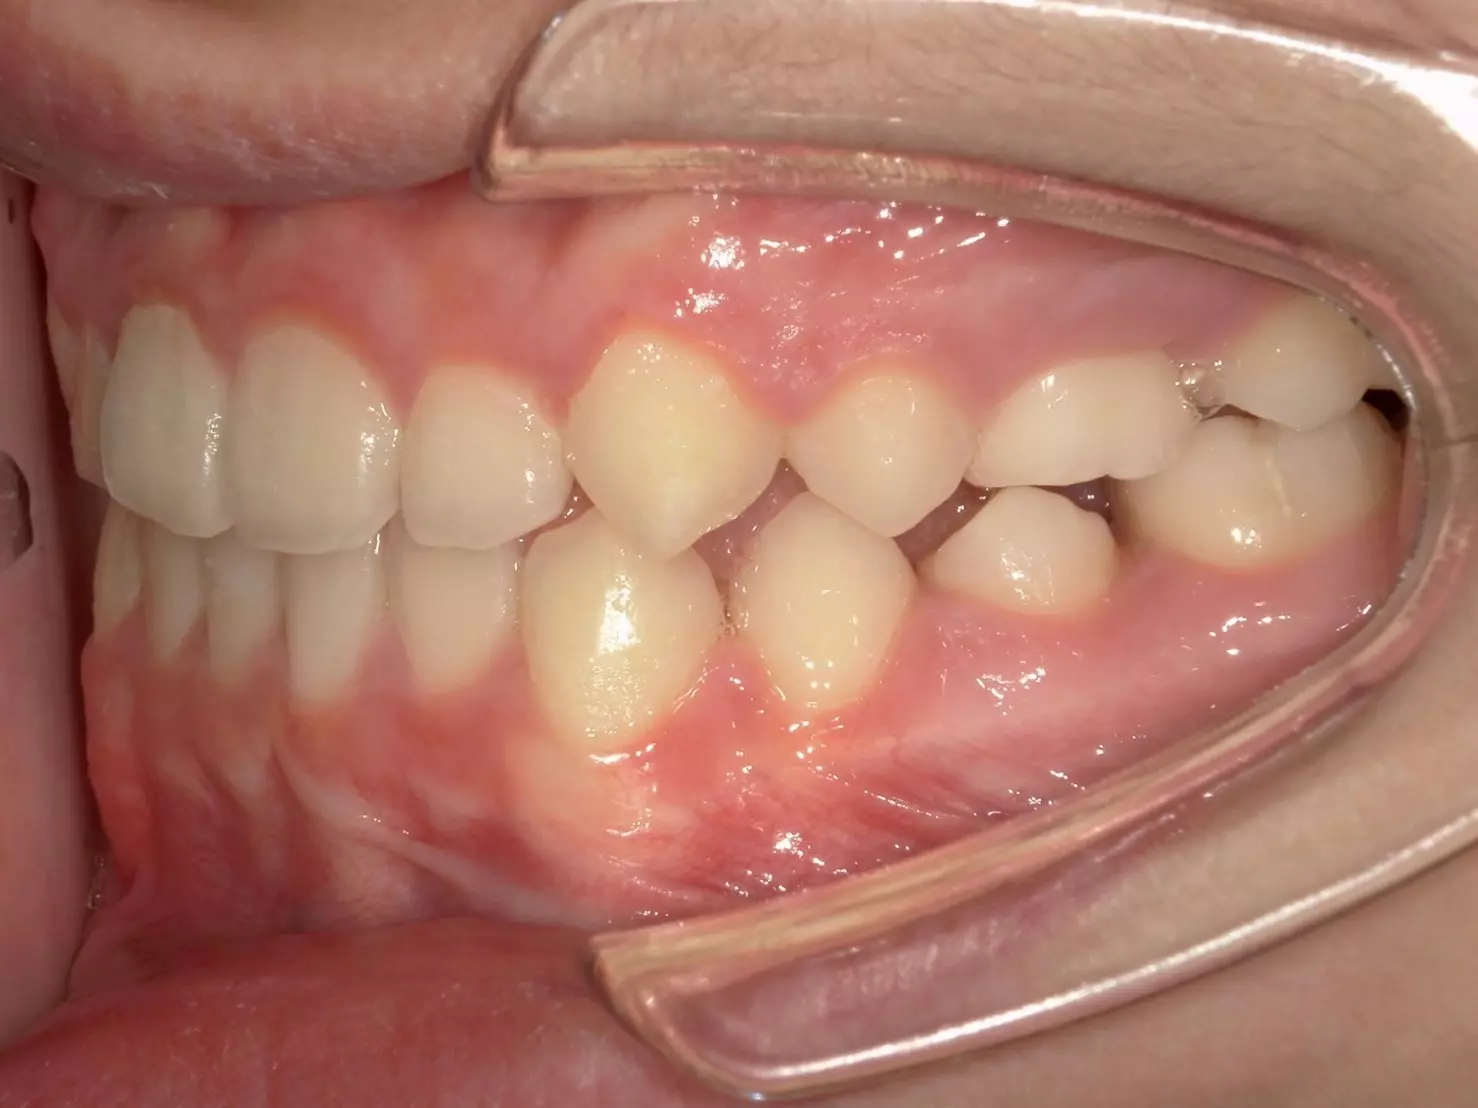

↑治療後

治療結束後,男孩的上顎恢復了正常生長,下顎也回到了理想位置。齒列整齊了,咬合也正常了,最重要的是他的笑容回來了!

父母告訴我們,孩子現在不僅願意開懷大笑,飲食也變得正常許多,整個人更有自信。這對一個正在成長的孩子來說,是非常寶貴的轉變。